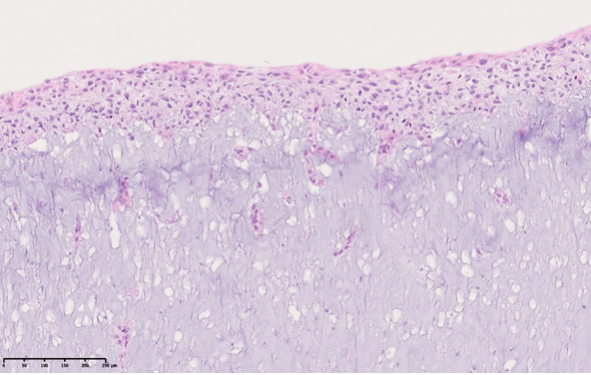

Das maligne Melanom ist eine der aggressivsten Formen von Hautkrebs und schwer zu behandeln. Um neue Therapieansätze zu entwickeln, ist es entscheidend, die Wechselwirkungen zwischen Tumorzellen und dem Immunsystem besser zu verstehen. Bisherige Forschungsmethoden basieren oft auf Tiermodellen, die nur begrenzt auf den Menschen übertragbar sind. Unser Ziel ist es daher, ein innovatives 3D-biogedrucktes Hautmodell zu etablieren, das die natürliche Tumorumgebung realistisch nachbildet. Dazu werden menschliche Fibroblasten und Keratinozyten in Mikro-Chips gedruckt und Melanom-Spheroide in das Modell integriert. In der Haut spielen dendritische Zellen (DC) und Langerhans-Zellen eine zentrale Rolle in der Immunabwehr und der Antitumor-Immunität. Tumorzellen nutzen jedoch Mechanismen, um deren Funktion zu unterdrücken. Um diese Prozesse genauer zu erforschen, differenzieren wir verschiedene DC-Subtypen und Langerhans-Zellen aus Stammzellen – ohne den Einsatz tierischer Zusätze. Durch die Kombination dieser Komponenten wollen wir die Wechselwirkungen zwischen Melanomzellen und Immunzellen in einem realistischen Hautmodell besser untersuchen. Dies ist besonders relevant für die Entwicklung innovativer Immuntherapien gegen das Melanom.